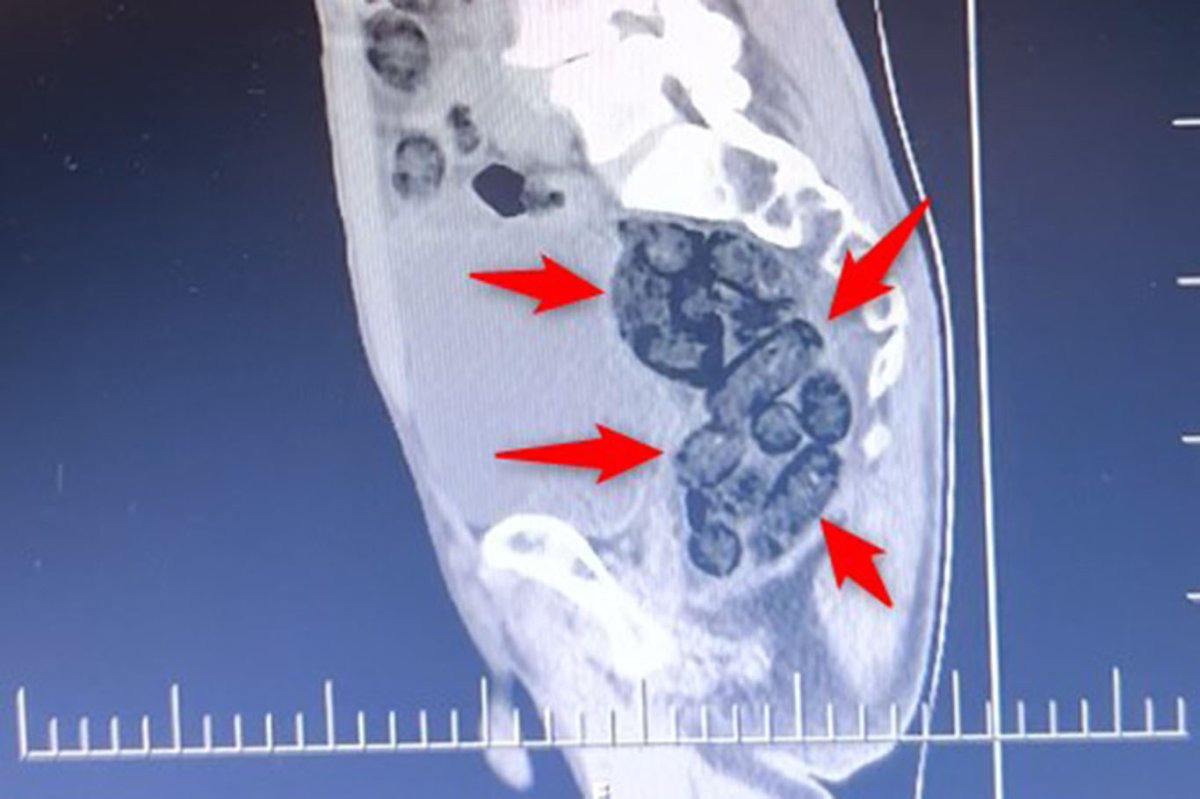

Batman'da durdurulan bir otobüste yolcu olarak bulunan yabancı uyruklu şahsın midesinden 64 parça halinde 472 gram metamfetamin ele geçirilirken, şüpheli tutuklanarak cezaevine gönderildi.

İl girişinde durdurulan bir otobüste yolcu olarak bulunan yabancı uyruklu bir şahıs üzerinde yapılan kontrollerde, şahsın midesinde 64 parça halinde toplam 472 gram metamfetamin maddesi tespit edilerek ele geçirildi.